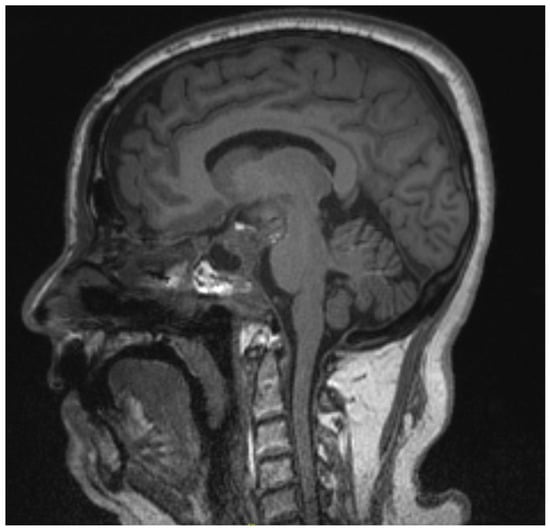

2.2. Case 2